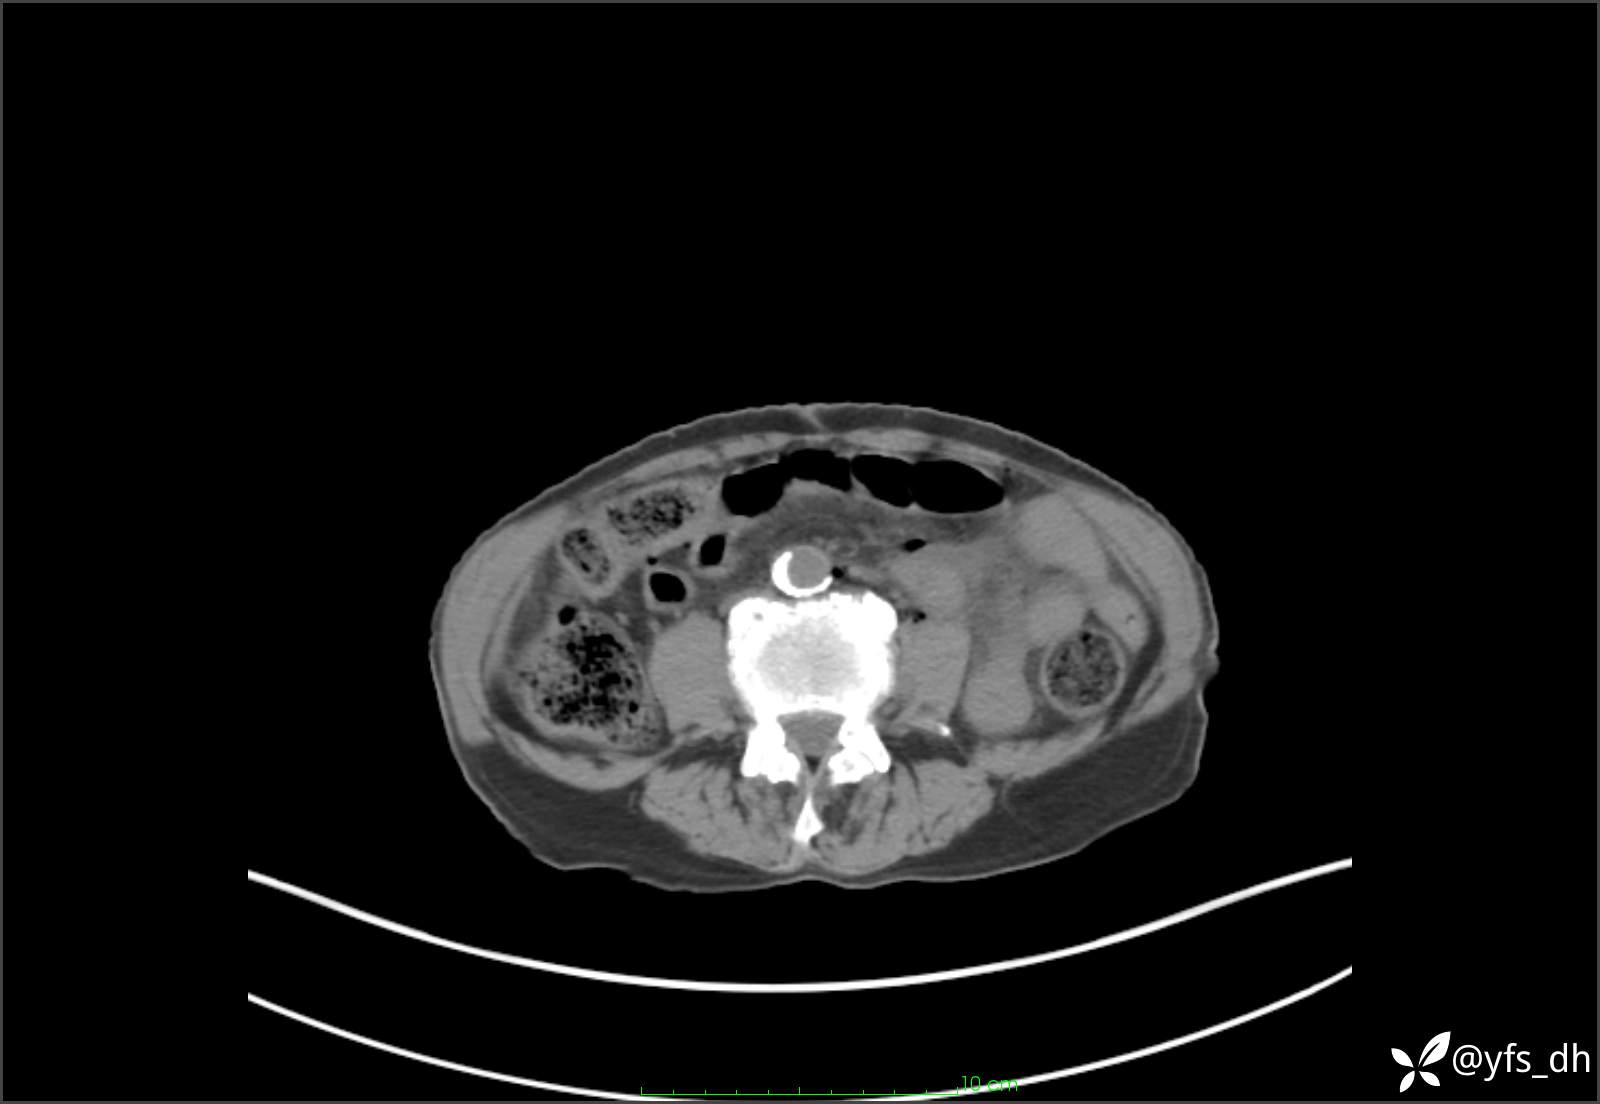

1.简要病史:患者4天前突发上腹部疼痛不适,但可以忍受。3小时前饭后突然加重,不能忍受后就诊。

2.简要手术记录:术中见腹盆腔大量肠液及粪便,乙状结肠中下段见一约3cm的破口。